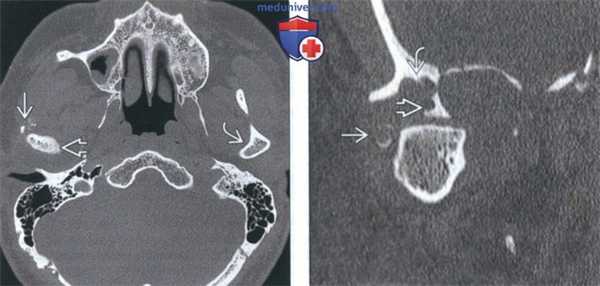

(Слева) КТ с КУ, мягкотканное окно. Другой пример хондросаркомы жевательного пространства, на этот раз без кальцификатов. Образование низкой плотности окружает ветвь нижней челюаи и распространяется вокруг венечного отростка и мыщелка.

(Справа) КТ в костном окне, аксиальная проекция. Мыщелок и шейка нижней челюсти деформированы и содержат кальцификаты. Отсутствие характерных кальцификатов в мягкотканной части опухоли делает постановку диагноза затруднительной.